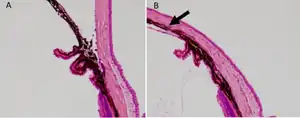

b) Anterior segment of laser-treated a) and control eye was histologically assessed. The arrow indicates the closed angle induced by laser photocoagulation.